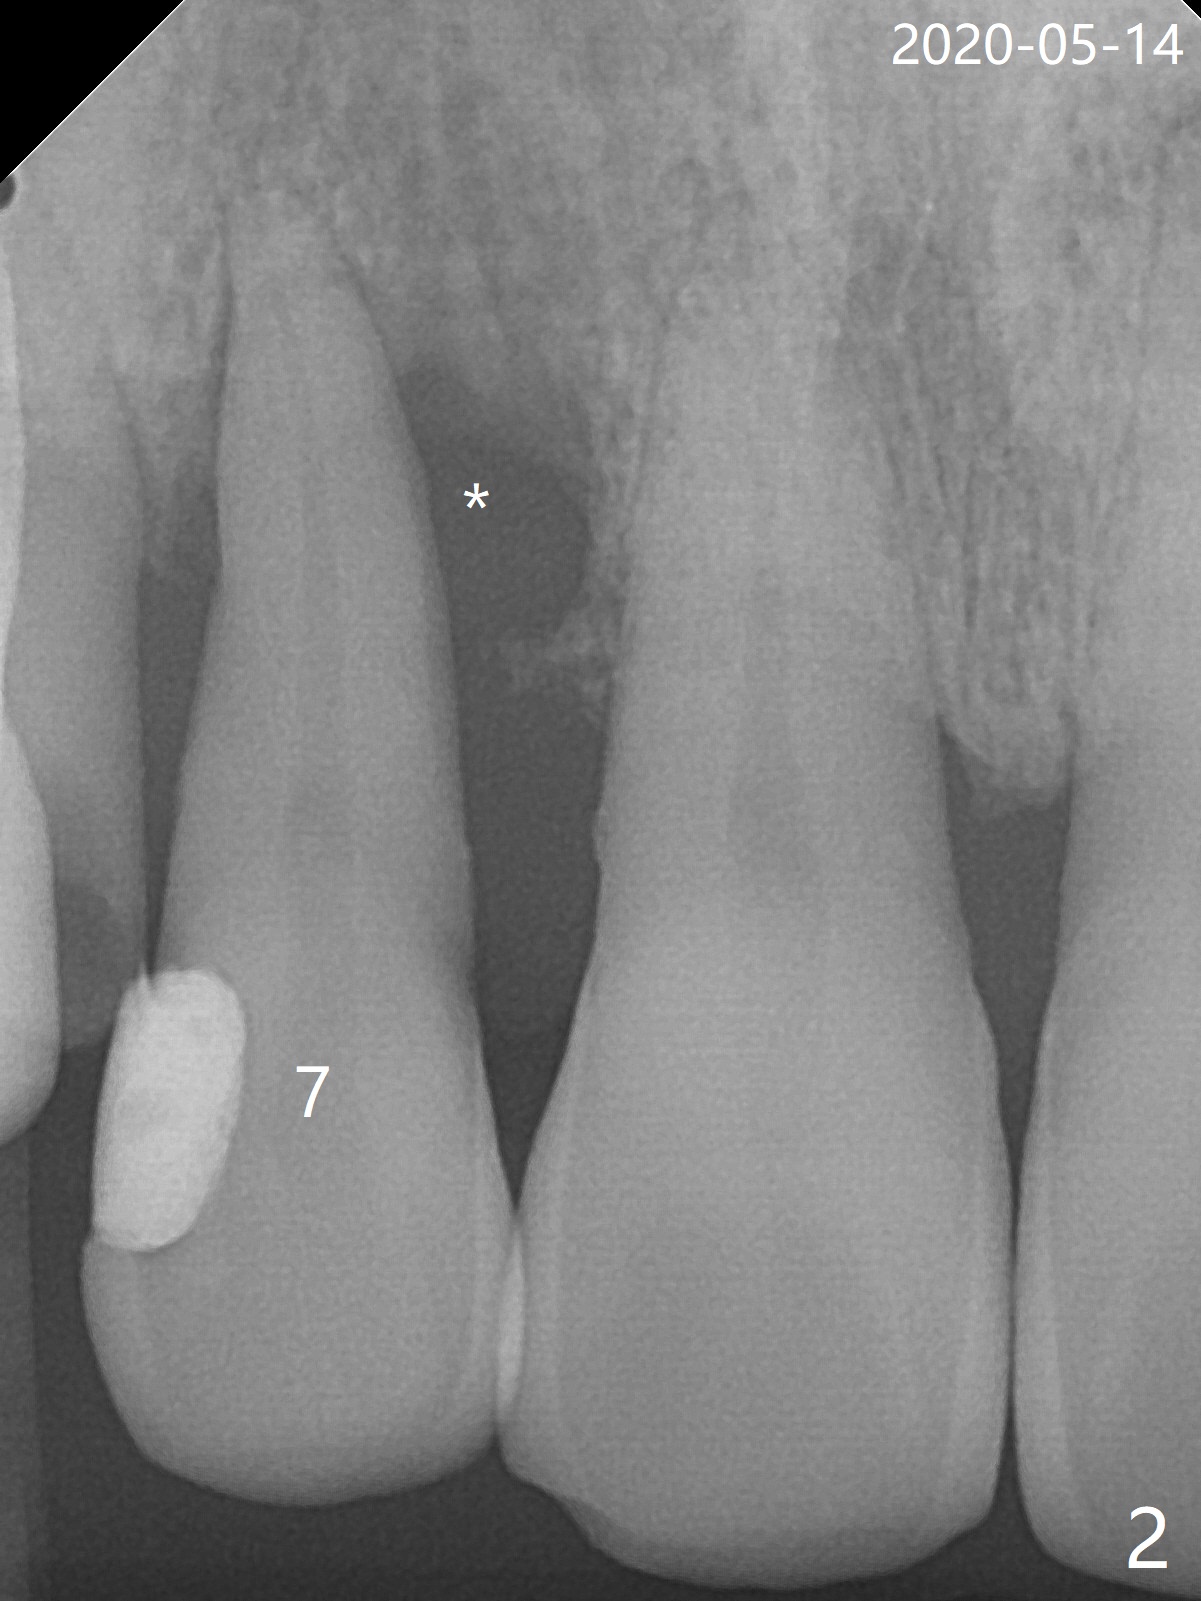

Lateral Implant/Canine Post

The tooth #7 (52 y/o, M, smoker) has mobility 2 months post #24/26, 30 implant placement without provisional (Fig.1,2) and seems to be necessary to be extracted for implant, while post and crown will be placed at #6 (Fig.3).